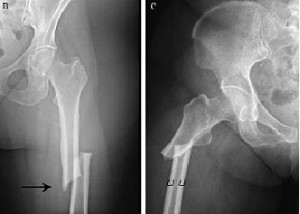

Luego de un uso promedio de 8 años, los bifosfonatos mostraban tejido cortical más mineralizado pero con menor resistencia al inicio y progresión de la fractura femoral. PNAS, 31 de julio de 2017